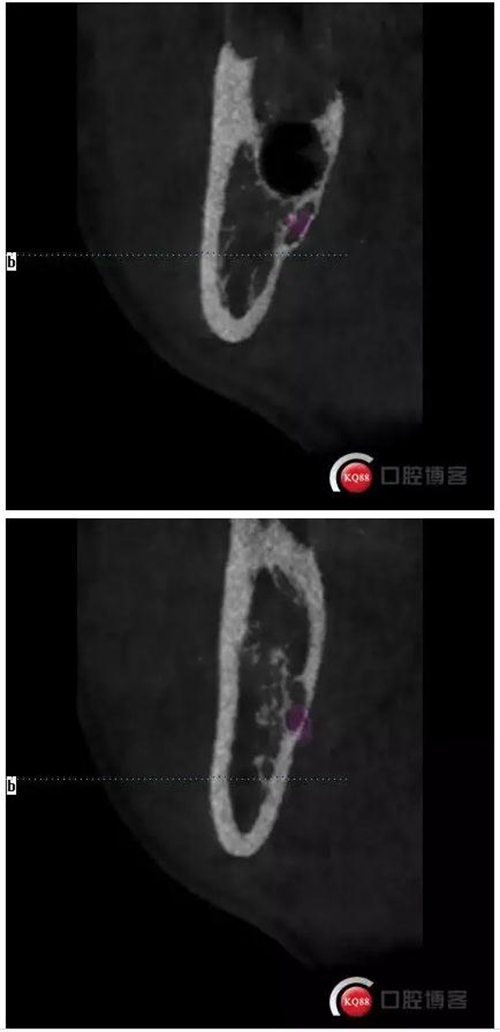

下面CBCT,可以看到兩個(gè)牙根的根尖三分之一在神經(jīng)管里面。

CBCT神經(jīng)管標(biāo)線,可以看到標(biāo)線不能連續(xù),中間被阻斷。

下面拔除后的片子,可以清楚的看到,牙根穿破神經(jīng)管。

1500633362_825152.jpg拔除后。 可以看到神經(jīng)管皮質(zhì)骨的不連續(xù)。